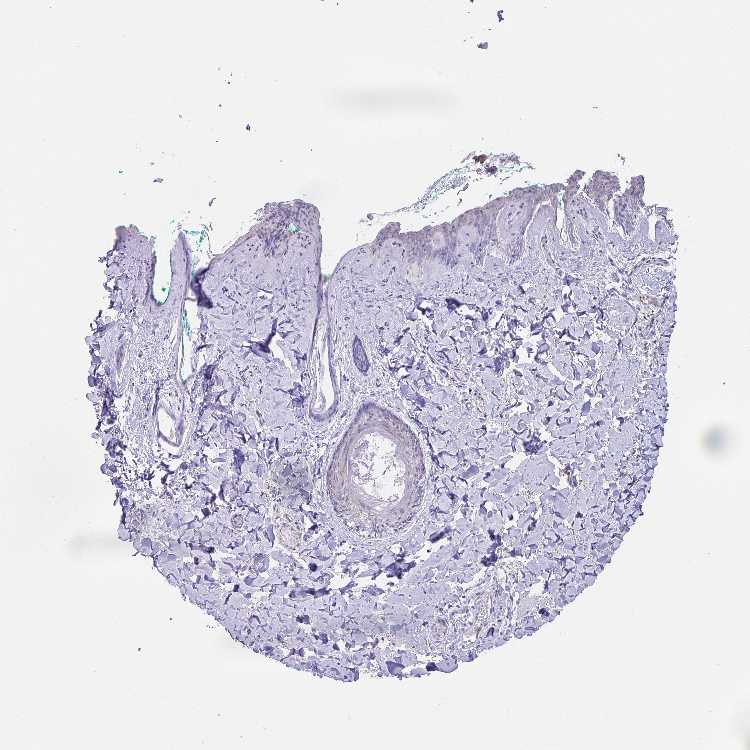

SKIN 2 - Antibody stainingi

Antibody staining in the annotated cell types in the current human tissue is reported as not detected, low, medium, or high, based on conventional immunohistochemistry profiling in selected tissues. This score is based on the combination of the staining intensity and fraction of stained cells.

Each image is clickable and will lead to virtual microscopy that enables deeper exploration of all samples and also displays staining intensity scores, fraction scores and subcellular localization as well as patient and tissue information for each sample.

Antibody HPA028402Antibody HPA043443

Epidermal cells Not detectedNot detected